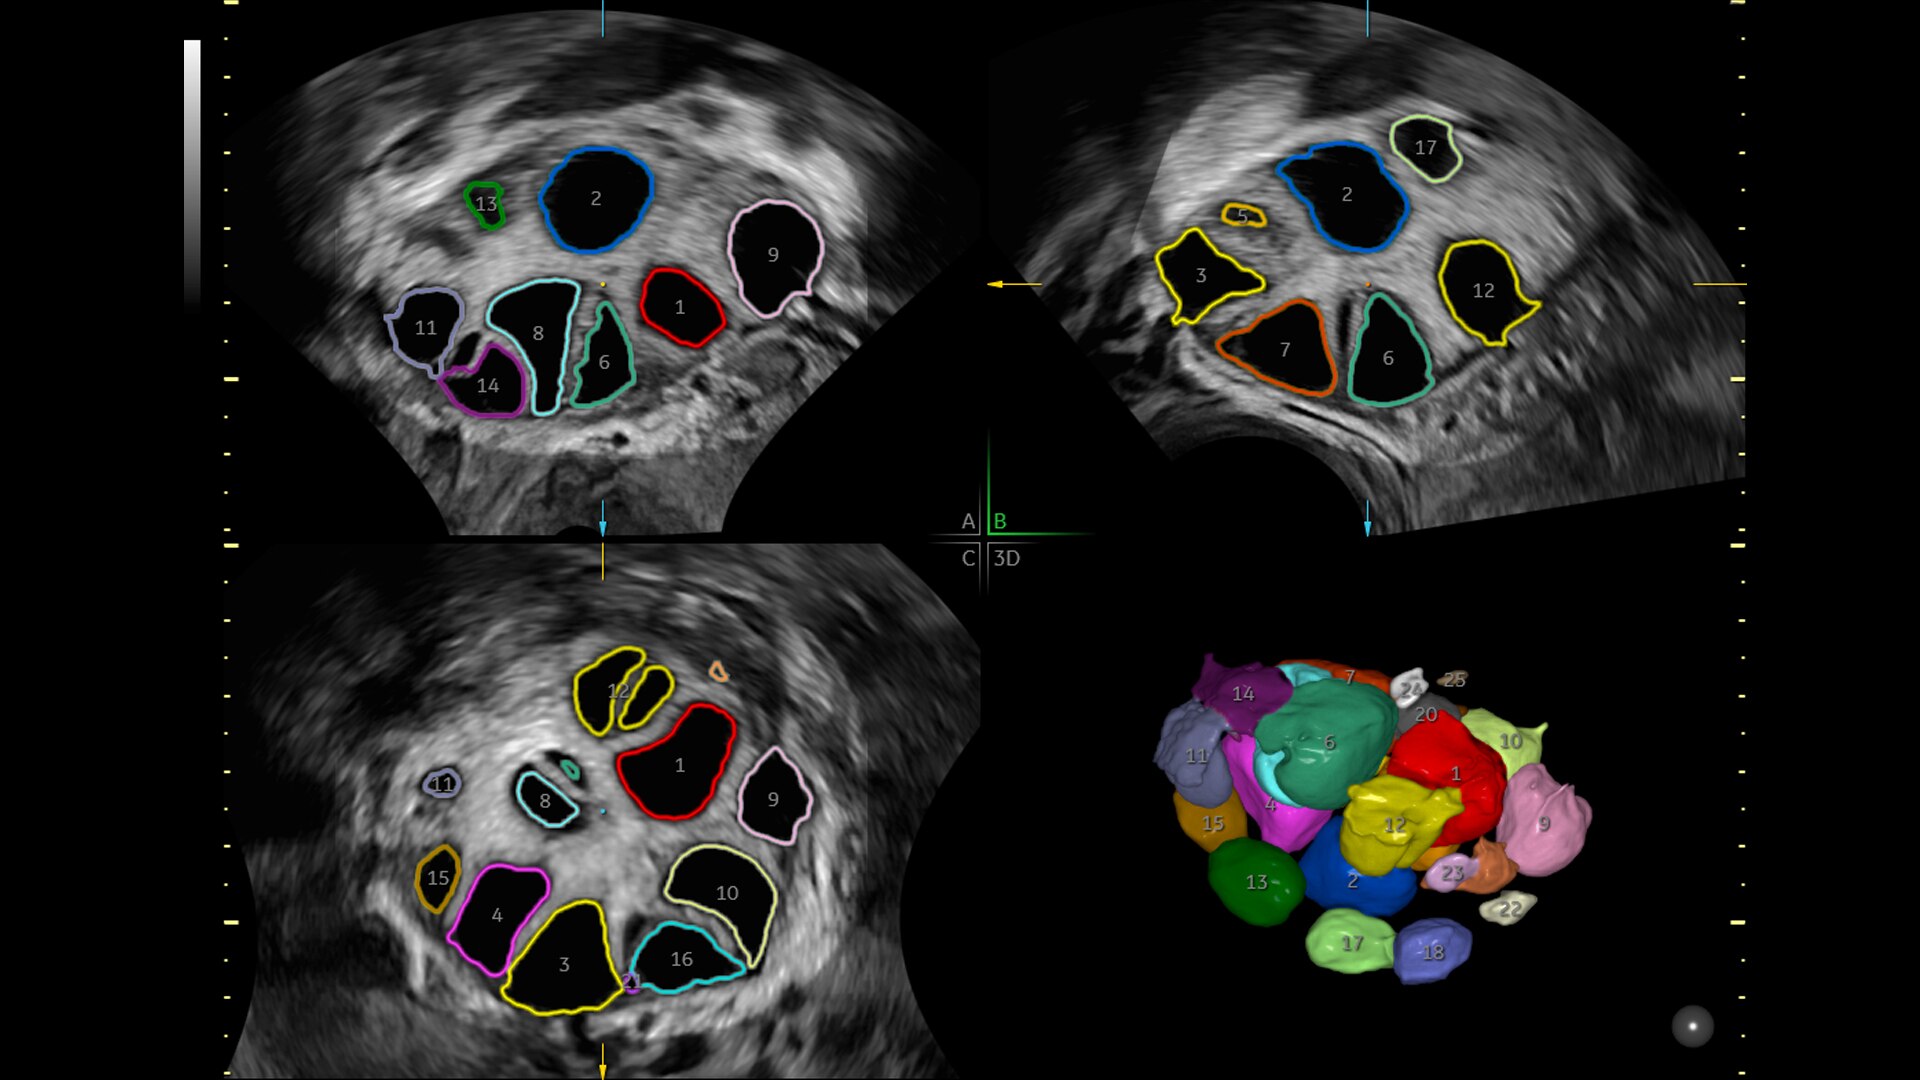

SonoGYN

Combines our Uterine Trace tool and Fibroid Mapping feature, an AI reporting tool that standardizes and streamlines fibroid documentation by mapping, measuring, and classifying fibroids in 3D.